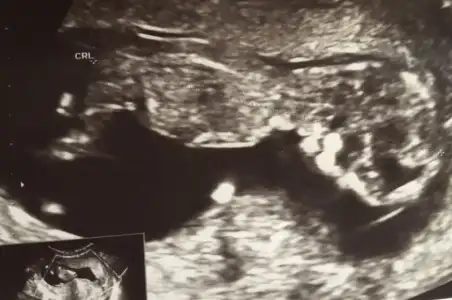

Ilk bebeginmiCanım çok teşekkürler. 3 ayı bitirmiş olacağım bir sonraki kontrolde, doktordan izin alır almaz yürüyüşteyim inşallah.

simsi erkek derse millete nasil soyliycem bilmiyorum